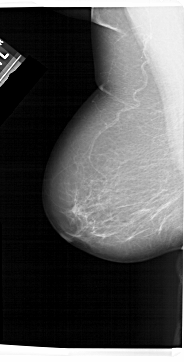

A_1309_1.LEFT_MLO

LEFT_MLO LINES 6871 PIXELS_PER_LINE 3496 BITS_PER_PIXEL 12 RESOLUTION 43.5 NON_OVERLAY